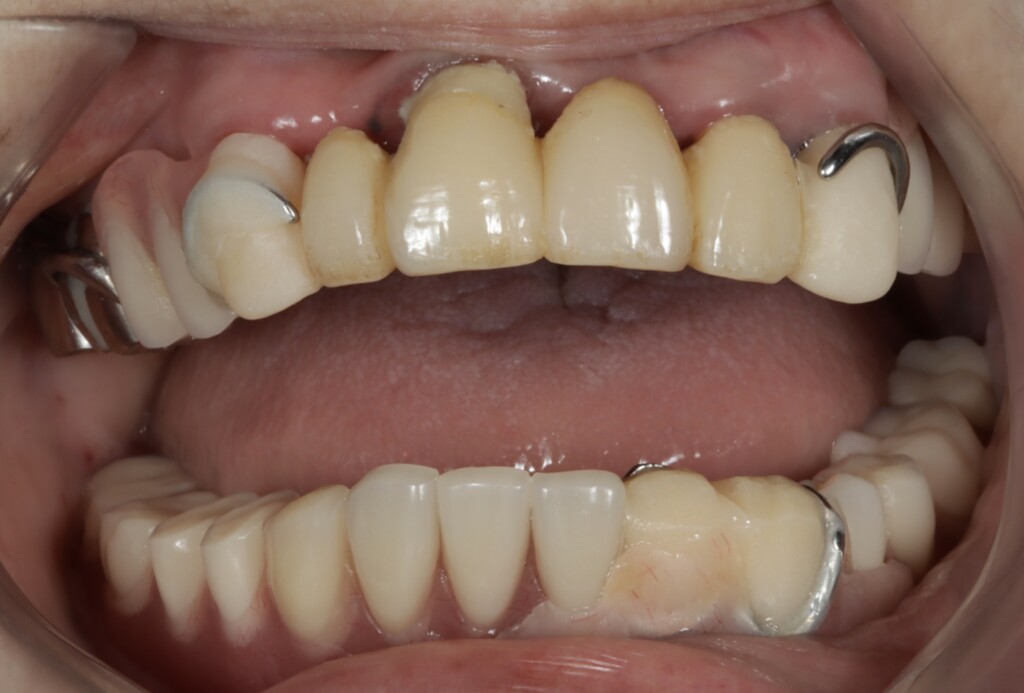

写真1:口腔内の正面観

*下顎は部分入れ歯を修理した総入れ歯が装着されている

写真2:乱れた噛み合わせの平面

写真3:下顎の歯ぐきの状態

写真1・2の下顎の義歯は、もともと部分入れ歯として使用されていたものを、抜歯に伴い修理し、総入れ歯として使用されていました。総入れ歯と部分入れ歯は同じ「入れ歯」ですが、設計のコンセプトは大きく異なります。

今回の義歯は、もともと部分入れ歯として作製されたものを修理して使用していたため、こうした「総入れ歯としての安定に必要な設計」が十分ではありませんでした。その結果、食事のたびに動いてしまう状態につながっていたと考えられます。